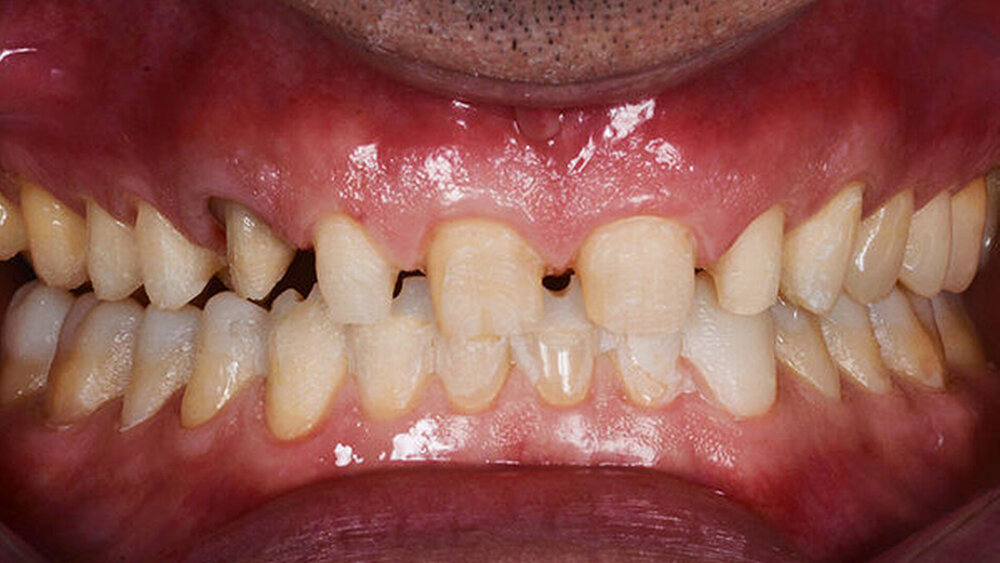

2015 stellte sich ein 47 Jahre alter Mann mit Schmerzen im TMG (Temporomandibulargelenk) vor. Er hatte außerdem ein ästhetisches Anliegen, da ein Stück vom Veneer eines mittleren oberen Schneidezahns abgebrochen war (Abb. 1–3). Die klinische und radiografische Analyse (Abb. 4) ergab einen Verlust der Bisshöhe und der Zahnsubstanz aufgrund von Bruxismus.